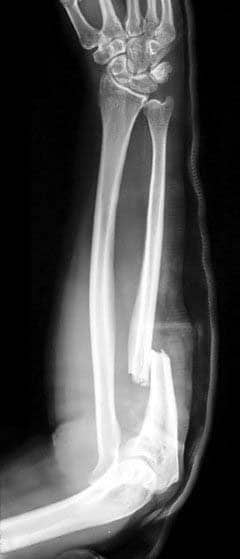

The ulna is a long bone in the forearm. It lies medially and parallel to the radius, the second of the forearm bones. The ulna acts as the stabilising bone, with the radius pivoting to produce movement. Proximally, the ulna articulates with the humerus at the elbow joint. Distally, the ulna articulates with the radius, forming the distal radio-ulnar joint. In this article, we shall look at the anatomy of the ulna – its bony landmarks, muscle attachments and clinical correlations. By Anatomography [CC-BY-SA-2.1-jp], via Wikimedia Commons Fig 1.0Overview of the anatomical position of the ulna in the upper limb. Pro Feature - 3D Model You've Discovered a Pro Feature Access our 3D Model Library Explore, cut, dissect, annotate and manipulate our 3D models to visualise anatomy in a dynamic, interactive way. Learn More Proximal Osteology and Articulation The proximal end of the ulna articulates with the trochlea of the humerus. To enable movement at the elbow joint, the ulna has a specialised structure, with bony prominences for muscle attachment. Important landmarks of the proximal ulna are the olecranon, coronoid process, trochlear notch, radial notch and the tuberosity of ulna: Olecranon – a large projection of bone that extends proximally, forming part of trochlear notch. It can be palpated as the ‘tip’ of the elbow. The triceps brachii muscle attaches to its superior surface. Coronoid process – this ridge of bone projects outwards anteriorly, forming part of the trochlear notch. Trochlear notch – formed by the olecranon and coronoid process. It is wrench shaped, and articulates with the trochlea of the humerus. Radial notch – located on the lateral surface of the trochlear notch, this area articulates with the head of the radius. Tuberosity of ulna – a roughening immediately distal to the coronoid process. It is where the brachialis muscle attaches. By TeachMeSeries Ltd (2025) Fig 2The bony landmarks of the proximal ulna. Shaft of the Ulna The ulnar shaft is triangular in shape, with three borders and three surfaces. As it moves distally, it decreases in width. The three surfaces: Anterior – site of attachment for the pronator quadratus muscle distally. Posterior – site of attachment for many muscles. Medial – unremarkable. The three borders: Posterior – palpable along the entire length of the forearm posteriorly Interosseous – site of attachment for the interosseous membrane, which spans the distance between the two forearm bones. Anterior – unremarkable. Distal Osteology and Articulations The distal end of the ulna is much smaller in diameter than the proximal end. It is mostly unremarkable, terminating in a rounded head, with distal projection – the ulnar styloid process. The head articulates with the ulnar notch of the radius to form the distal radio-ulnar joint. Clinical Relevance – Common Fractures of the Ulna The forearm is a common site for bone fractures. Here, we shall look at the common fracture types involving the ulna. A fracture of the ulna alone (not involving the radius) usually occurs as a result of the ulna being hit by an object. The shaft is the most likely site of fracture. In this situation, the normal muscle tone will pull the proximal ulna posteriorly. Less commonly, the olecranon process can be fractured. This is caused by the patient falling on a flexed elbow. The triceps brachii can displace part of the fragment proximally. The ulna and the radius are attached by the interosseous membrane. The force of a trauma to one bone can be transmitted to the other via this membrane. Thus, fractures of both the forearm bones are not uncommon. There are two classical fractures: Monteggia’s Fracture – Usually caused by a force from behind the ulna. The proximal shaft of ulna is fractured, and the head of the radius dislocates anteriorly at the elbow. Galeazzi’s Fracture – A fracture to the distal radius, with the ulna head dislocating at the distal radio-ulnar joint. By Jane Agnes [CC BY-SA 3.0], via Wikimedia Commons Fig 3Monteggia fracture of the radius and ulna Do you think you’re ready? Take the quiz below Pro Feature - Quiz The Ulna Question 1 of 3 Submitting... Skip Next Rate question: You scored 0% Skipped: 0/3 1800 More Questions Available Upgrade to TeachMeAnatomy Pro Challenge yourself with over 1800 multiple-choice questions to reinforce learning Learn More Rate This Article